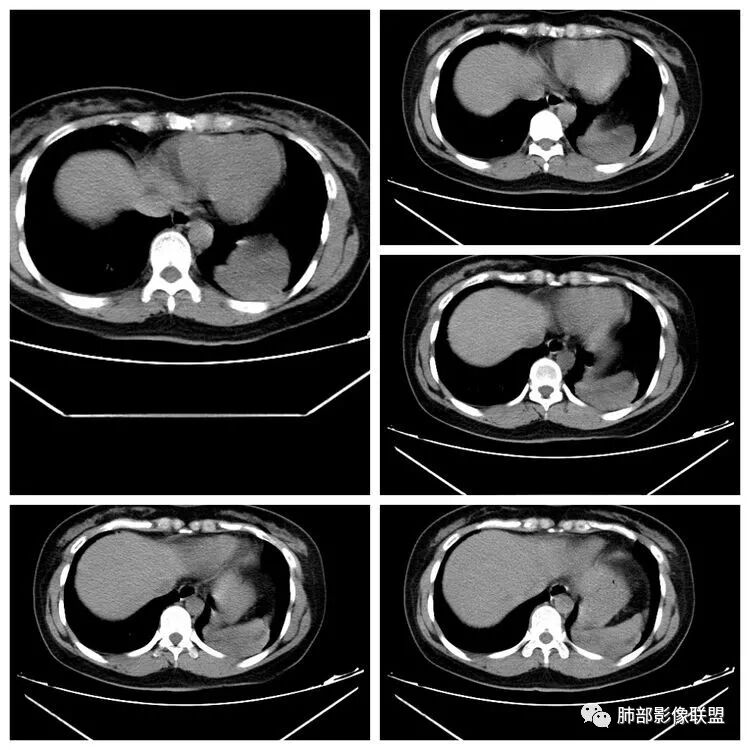

远方:

发晨读病例结果,大家意见都比较一致。手术病理如下:

最后结果:

结合影像及病理:

脏层胸膜来源孤立性纤维瘤

CT表现:1.多为来自胸膜单发肿块,轮廓较光滑,一般无分叶,可有包膜,可以有胸膜尾征。少数胸膜SFT可表现为带蒂肿块,为本病较为特征性表现。2.当肿瘤较小(小于5cm)时,平扫密度较均匀,为软组织密度,增强扫描呈轻中度均匀强化,少数肿瘤强化较明显。3.随着肿瘤的增大,发生粘液变性、囊变坏死概率增加,多表现为密度不均匀,并可有钙化,增强为轻中度不均匀强化,常表现为“地图样”。

潘军平老师关于定位点评——我们判断肺内肺外的依据:1、与胸膜的关系。主体在外面,宽基底与胸膜连接,胸膜掀起一般是肺外的依据。2.、与肺内结构的关系:附近血管、支气管被推移,未进入病灶(无血供的良性病变有时候要警惕除外),提示肺外。3、血供,肺部来源的一般肺部血供(隔离症除外,恶性肿瘤有时候会有差异,孤立性纤维瘤血供可以肺内来源)。